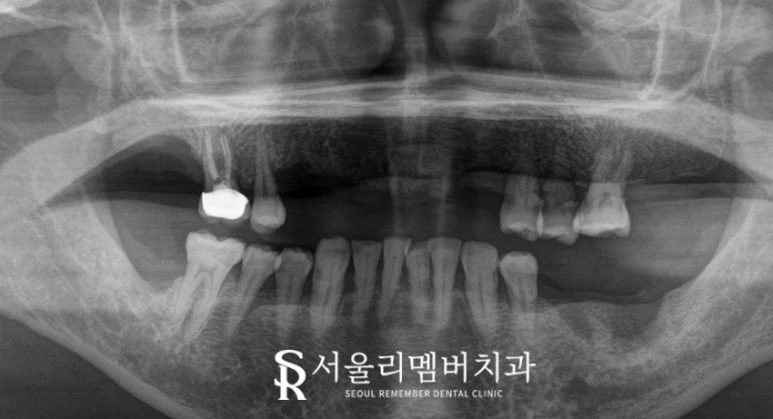

우선 자세한 진단을 내리기 위해 현재 상태를 확인했습니다.

상실된 전치부 치아들이 눈에 띄게 나타나고 있었으며

치은에 전체적으로 염증이 생겨 있었습니다.

이가 빠진 채로 오래 생활하시다 보니

치은의 기능이 퇴축되어 있었는데요.

신림역 치과 에서 좀 더 자세한 진단을 위해

엑스레이 촬영을 통해 확인해 보았습니다.

치조골 라인

상악에는 단 5개의 잔존치들이 남아있었습니다.

다행히 남아있는 곳들은 병소가 크게 진행되지 않아

그대로 살려둘 수 있을 것 같다는 판단이 들었는데요.